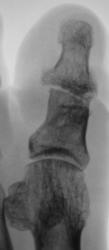

Травма 2 года тому. Пациент направлен хирургом на рентгенографию 1 пальца в связи с усиливающимися болями в области первого пальца. К вечеру боли носят "пекущий" характер (со слов пациента).